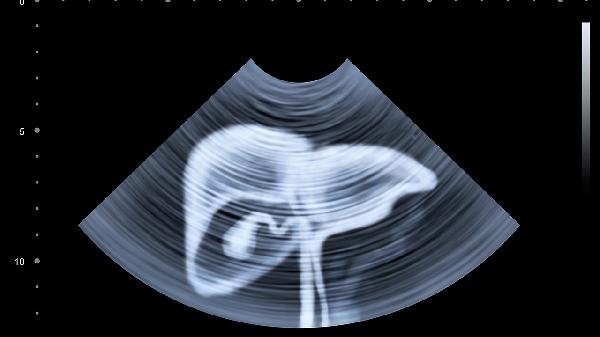

4、生殖系统疾病:如卵巢囊肿、盆腔炎。此类病症常伴有持续性或周期性下腹部隐痛,尤其是女性受其影响较大。若怀疑此类情况,应该咨询妇科通过超声检查等手段确诊,并遵循治疗方案,如药物或手术治疗。